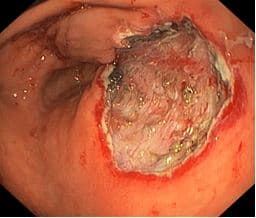

Диссекция

Выполнена диссекция в подслизистом слое (мы используем современное электрохирургическое оборудование последнего поколения - нож ERBE V/O режим Endocut Q), ближнем к мышечному, при помощи IT-knife «Olympus».

Область резекции слизистой оболочки в виде посткоагуляционного дефекта овальной формы, размером ~ 25 х 30мм, в дне дефекта отчетливо визуализируются соединительнотканные сплетения подслизистого слоя сетчатой структуры, пеньки тромбированных сосудов

На рисунке: Область резекции слизистой оболочки.